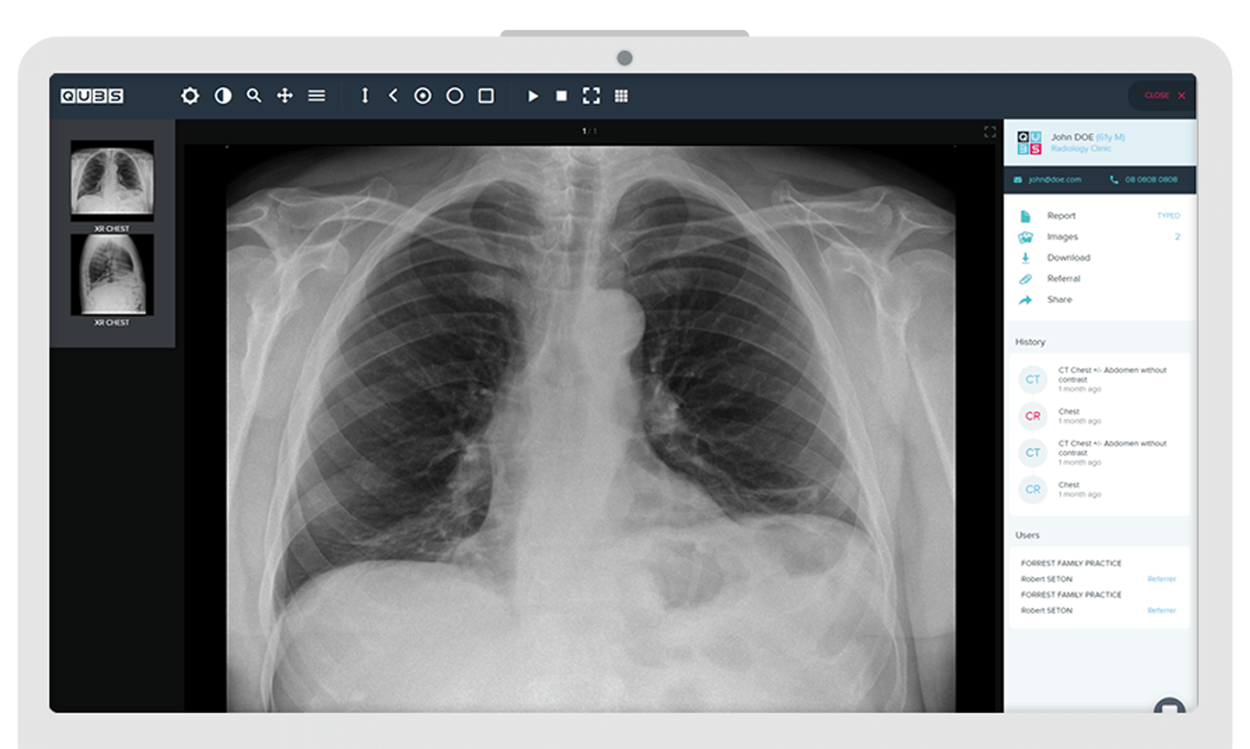

Accomplish more with cloud medical imaging

Connecting clinics, patients, referrers and specialists for better outcomes

Fully supported RIS and PACS image management, designed to scale with your needs. Fast, secure and cost-effective.

Review patient reports and images on the go, only moments after completion.

Radiology Information System to manage patients, scheduling, billing and reporting, in one place.